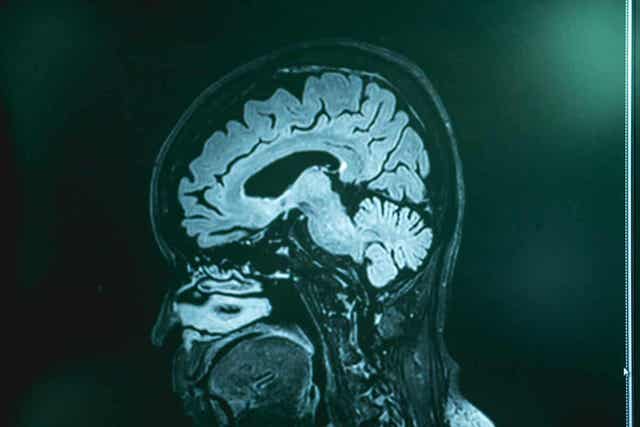

Zoals aangegeven in de MSD-handleidingen (Engelse link) kan deze ziekte alleen worden bevestigd door een lumbaalpunctie (en daaropvolgend onderzoek van het hersenvocht), en door een hersenbiopsie. Artsen voeren deze tests uit bij mensen met symptomen van PAM die in de afgelopen dagen in contact zijn geweest met onbehandeld zoet water.

Beeldvormend onderzoek (computertomografie en magnetische resonantie beeldvorming) kan daarentegen de ziekte niet opsporen, maar kan wel andere mogelijke gezondheidsproblemen uitsluiten. Zodra het cerebrospinaal vocht is verkregen voeren artsen kweken of genetische analyses uit op zoek naar het genoom van de amoebe.